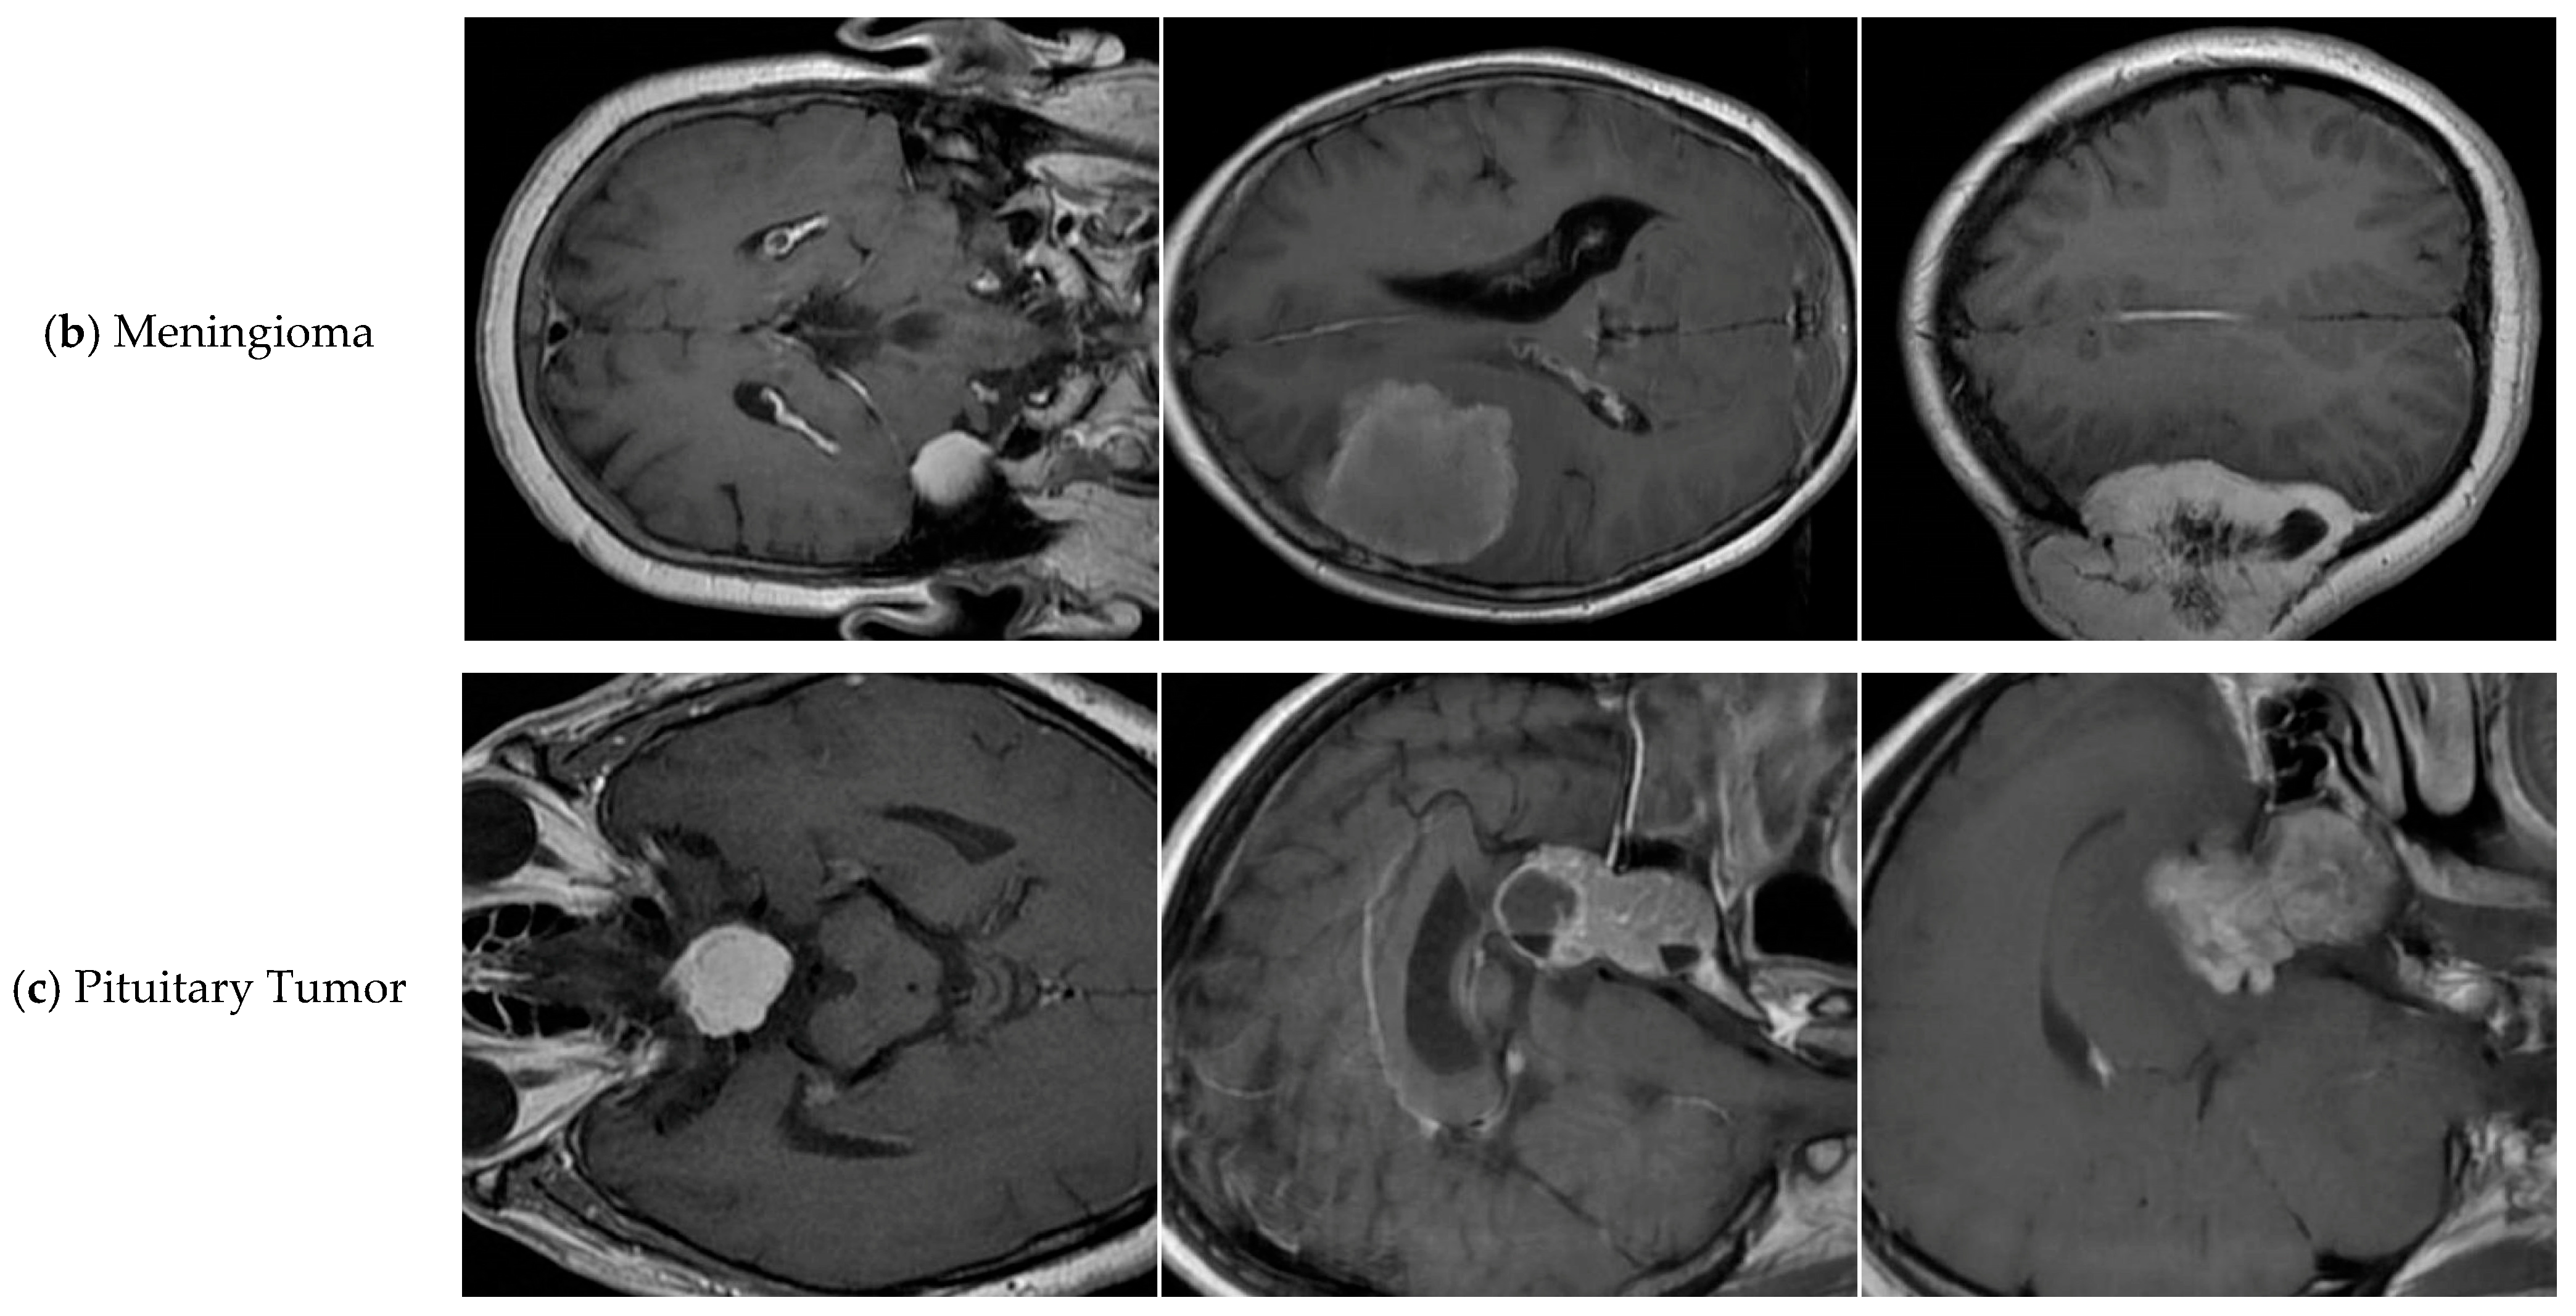

4.8. Discussion on Brain Tumor Classification Ability

- Roboflow. BRAIN TUMOR > Roboflow Universe. Available online: https://universe.roboflow.com/college-piawa/brain-tumor-j0l2c (accessed on 11 September 2025).

| Class | FALS-YOLO Correct Classification | FALS-YOLO Misclassification | YOLOv8-Seg Correct Classification | YOLOv8-Seg Misclassification |

|---|---|---|---|---|

| Glioma | 132 | 40 | 124 | 37 |

| Meningioma | 58 | 10 | 56 | 6 |

| Pituitary | 81 | 10 | 78 | 5 |

| Background | - | 31 | - | 42 |